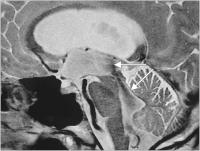

Abbildung 1: Das "flow void sign" ist bei Hydrozephaluspatienten meist sehr imponierend und reicht oft weit in den 3. und 4. Ventrikel (Pfeile) hinein. Als Ursache wird der pulsatile Liquorfluß angesehen. Einige Arbeitsgruppen versuchten, diese Ausdehnung zu quantifizieren, und leiteten daraus ein Ansprechen oder Nichtansprechen auf eine Shuntoperation ab.